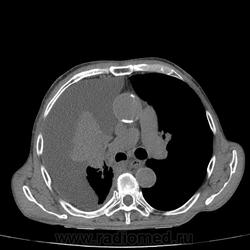

Пожилой мужчина, лечился по н/д правостороннней пневмонии в терап/отделении. Жалобы на одышку, кашель. По результатам Р-контроля после лечения направлен на КТ легких с диагнозом: плеврит справа, распад? В корне правого легкого вижу объёмное образование, с распадом. Смущают размеры плеврита,очень много жидкости, почти до 3 ребра. Анализы крови спокойные- L4,0-6,6, СОЭ 12-16мм. Неужто ТБС, отсев бы был при таком огромном поражении. В посеве мокроты-100% высев клебсиэллы пневмоние. Мокрота на общий анализ в работе-собирает с трудом, изза отсутствия мокроты. Плевральную пункцию еще не проводили. Н азначила бронхоскопию и плеврал пункцию. Как думаете, уважаемые коллеги, это онкопроцесс или тбс распад?

Самое интересное забыла показать- может это 100% навеет на мысль об опухолевом процессе, остеолитическая деструкция позвонка?

Не смотря дайкомы, только по рентгенограмме, предположил бы центральный рак правого легкого. Потому что большой гидроторакс, без смещения средостения в здоровую сторону, как правило, соответствует раковому ателектазу.

Коллеги, распада там нет, это вас медиастинальное окно подвело. В грудине тоже все в порядке. Да и компрессия позвонка "старая".

Небольшое количество увеличенных лимфоузлов, и те - не сказать, чтоб были очень крупными. От эмпиемы до онкологии... Умеренное количество жидкости в перикарде, толщиной слоя до 13-14 мм. При подобной картине не вижу смысла гадать по сжатому лёгкому, пишу так: массивный выпот справа, около 2500 мл, диафрагма оттеснена жидкостью каудально, печень (!!!) смещена каудально и вправо. Легкое справа значительно компрессировано жидкостью, оценка проходимости бронхов и состояния легочной паренхимы (кроме имеющейся эмфиземы) практически невозможна. Необходима пункция плевральной полости справа (цитология, ВК, посев на микрофлору и проч), КТ-контроль после эвакуации жидкости.